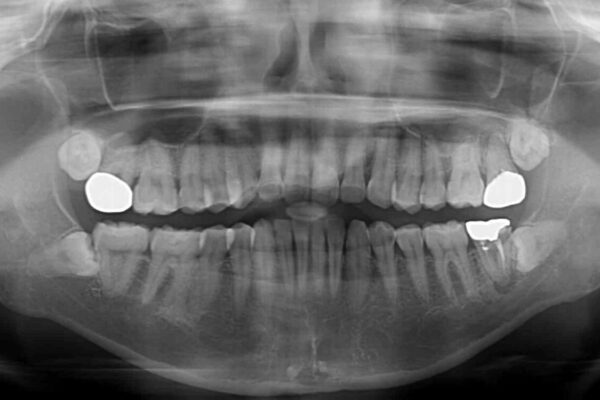

上下前歯や奥歯の虫歯治療を希望して来院された患者様です。

全顎的にむし歯が多く、根管治療の必要な奥歯や、審美的に気になっている前歯を中心にオールセラミッククラウンにて補綴治療を行うこととしました。

治療前

• むし歯だらけの前歯をオールセラミッククラウンできれいに 治療前画像